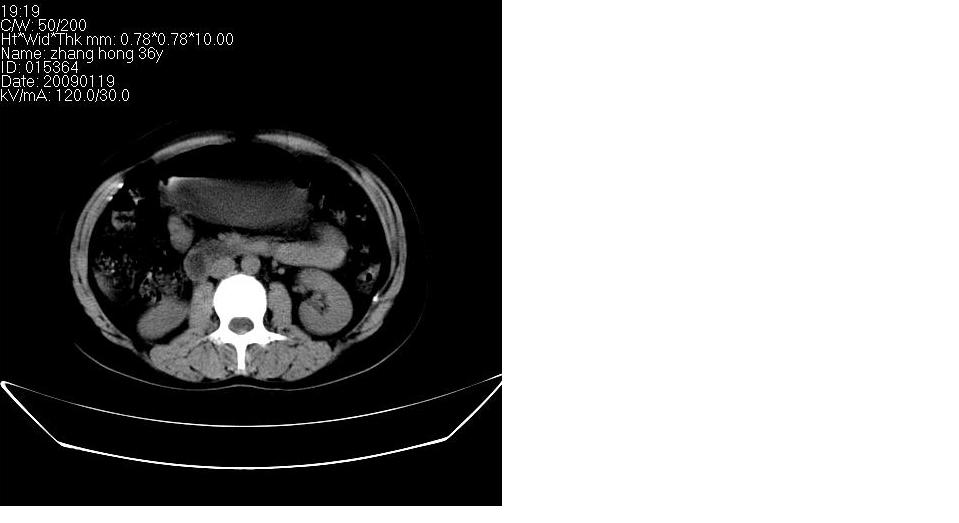

女 36岁,腹痛月余,b超提示肝左叶占位,腹水。

肝脏左叶明显增大,各叶比例失调,左叶实质内不均匀低密度影,似乎有肝内胆管的扩张,没有增强实在不好判断,不知患者肝功能是否正常,我觉得象胆管细胞癌。

肝脏左叶明显增大,各叶比例失调,左叶实质内不均匀低密度影,增强!

从这个平扫图像看,只能诊断肝左叶占位,具体性质没有增强扫描不能诊断,只能说肝左叶低密度影,建议增强扫描进一步检查。

1)考虑肝左叶肝癌;建议行进一步检查。2)肝硬化,脾稍大。3)双侧少量胸腔积液。

肝脏左叶明显增大,且左叶实质内不均匀低密度影。考虑左叶占位??建议增强后再讨论。